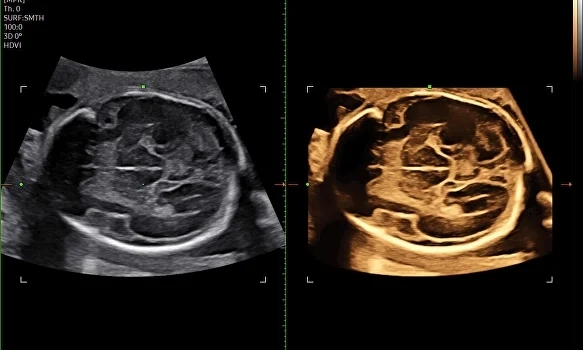

• Расширенные режимы 2D, 3D и 4D для акушерства и гинекологии;

Безупречная картинка в 3D и 4D

Совершенно новый уровень визуализации плода с потрясающим качеством. Samsung Z20 открывает широкие возможности для диагностики и позволяет врачам работать максимально эффективно.